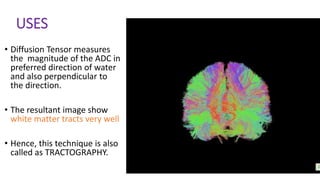

USES

• Diffusion Tensor measures

the magnitude of the ADC in

preferred direction of water

and also perpendicular to

the direction.

• The resultant image show

white matter tracts very well

• Hence, this technique is also

called as TRACTOGRAPHY.